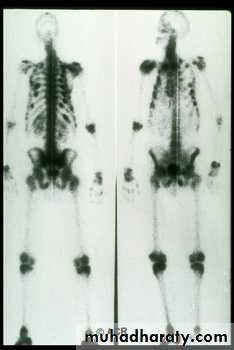

Hyperparathyroidism

Xrays:

sub-periosteal resorptionpepper pot skull

rugger jersey spine

cystic brown tumours

Xrays:sub-periosteal resorption

pepper pot skull